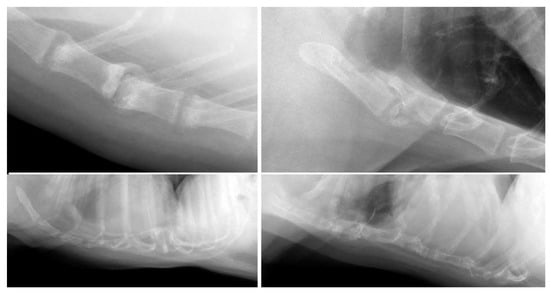

| Post-trauma (n = 12) | Dislocation (n = 5); collapse (n = 8); fracture (n = 2) | Labrador Retriever (3/62); mixed (2/145); Alaskan Malamute (1/4); Boxer (1/13); Chihuahua (1/28); Chow Chow (1/3); German Shepherd (1/21); Labradoodle (1/22); Welsh Springer Spaniel (1/3) |

| Post-trauma (n = 3) | Dislocation (n = 3) | Domestic Shorthair (3/112) |